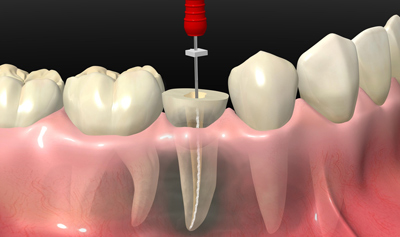

Endodoncia